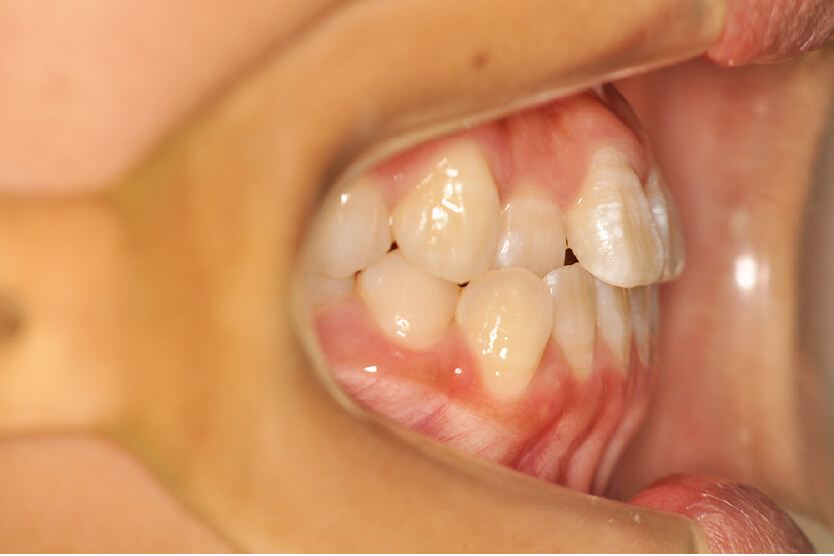

| 初診時 年齢 |

12歳 | 性 別 | 女性 |

| 治療期間 | 1年5か月 | 費 用 | 矯正施術料:750,000円 調整料:4,000円/月 |

| 治療内容の詳細 | 初診時12歳の女性で、上顎前歯部の反対咬合を気にされ来院されました。 検査の結果、下顎前突、上顎前歯部叢生および上顎側切歯反対咬合を伴うアングルⅢ級不正咬合と診断しました。 治療としては、リンガルアーチを使用して、上顎側切歯を前方へ移動させ、反対咬合の改善を行い、マウスピース型矯正装置(インビザライン)で配列を行いました。 治療期間は1年5か月でした。 |